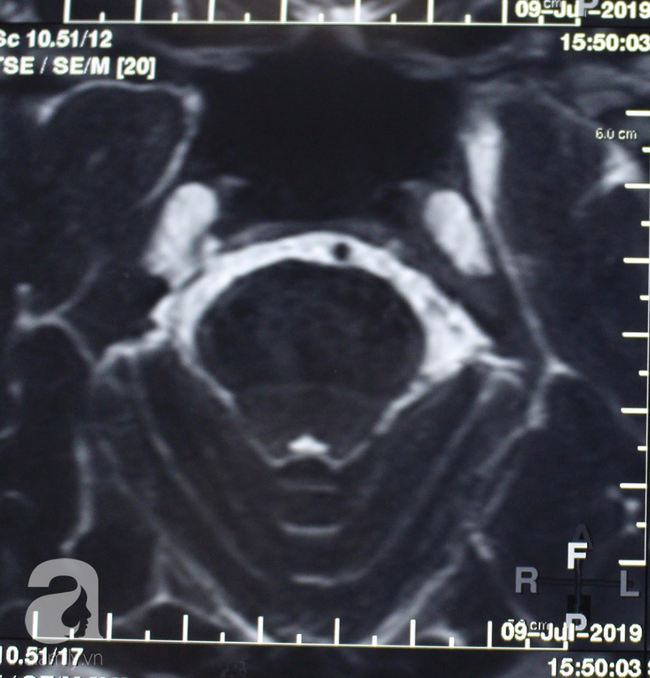

Gần đây khi không còn chịu đựng được, bệnh nhân đến bệnh viện CIH (TP.HCM) cầu cứu. Khai thác bệnh sử và thực hiện thăm khám kỹ càng, chụp MRI, bác sĩ chẩn đoán bệnh nhân bị đau dây thần kinh tam thoa (hay dây thần kinh số 5), rối loạn giấc ngủ.

Nguyên nhân của bệnh lý này được chứng minh là do dây thần kinh số 5 bị chèn ép bởi một hay nhiều nhánh mạch máu bên trong não.